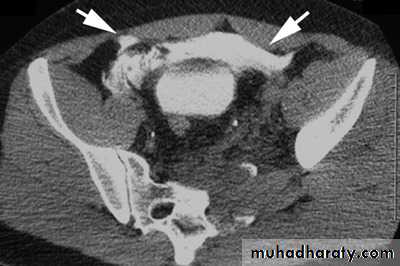

Bladder trauma

Intraperitoneal UB rupture(25%) :Result from direct blow to a distended UB.

Leaking of contrast to the peritoneal cavity

Extraperitoneal rupture (75%) :

Associated with pelvic bones fracture.